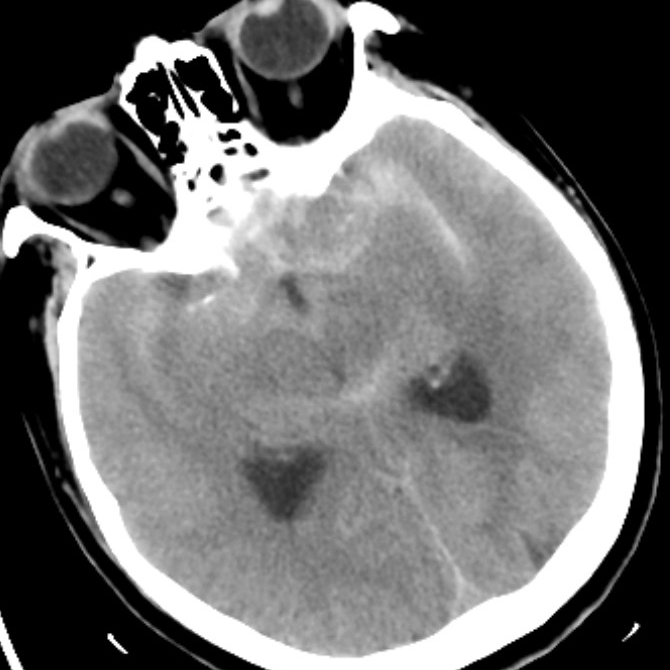

病例一为77岁女性患者,既往高血压病史。因“突发剧烈头痛伴恶心2天”前来清华大学附属垂杨柳医院急诊科就诊。头颅CT检查提示蛛网膜下腔出血,头颈动脉CTA提示右侧大脑中动脉M1段分叉处宽颈动脉瘤。神经外科脑血管病介入团队急诊为患者实施了全脑血管造影术(DSA),造影显示动脉瘤不规则,可见子囊,宽颈,主要累及下干。团队采取了支架辅助弹簧圈栓塞术,患者颅内“不定时炸弹”被成功拆除。动脉瘤达到致密栓塞,载瘤动脉通畅。住院半个月后顺利出院,无神经功能障碍。

▲头颅CT显示蛛网膜下腔出血